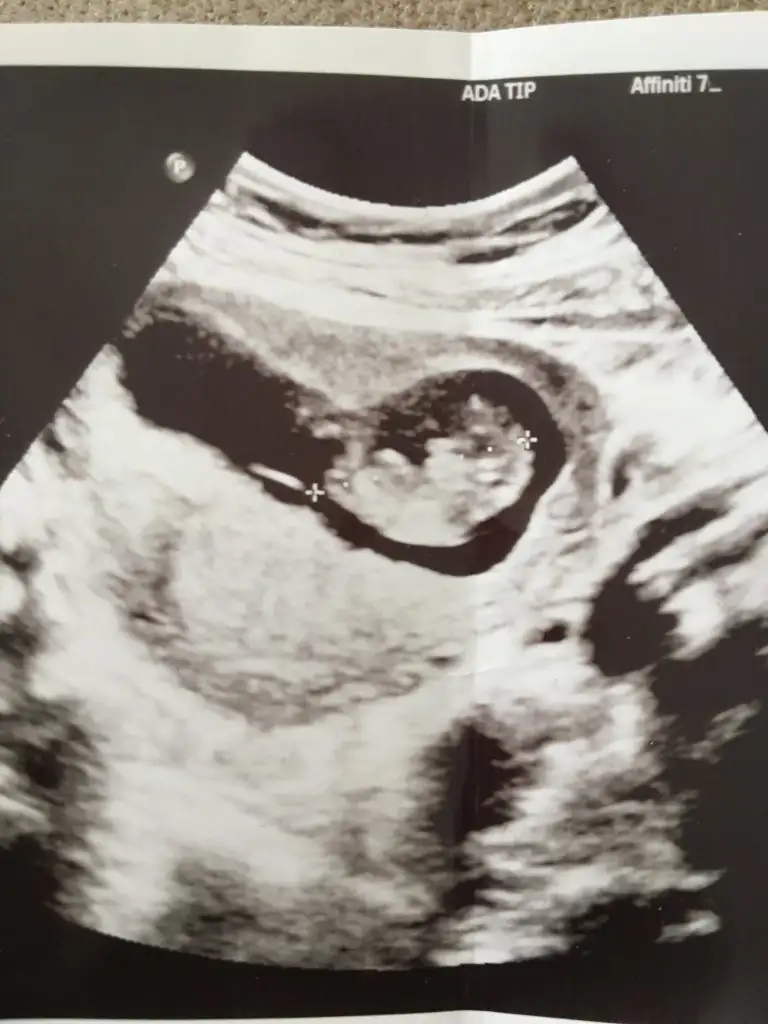

Merhabalar Tahmin yorumlarınızı heyecanla takip ediyorum. Bende sabırla 12. haftamızın dolmasını bekledim. Bir yorumda benim için yaparmısınız Buğün 12+1 olduk.